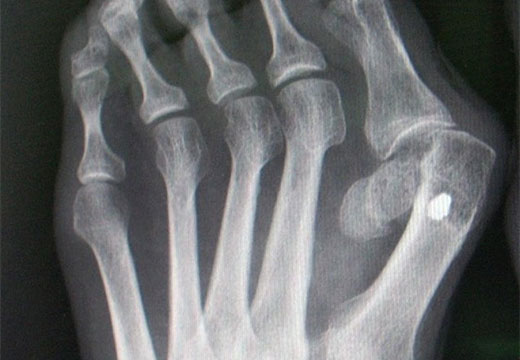

Диагноз выставляют, исходя из очной консультации, симптоматики и рентгена, где прицельно оценивается 1 палец и соседствующие анатомические структуры. Выраженность hallux valgus с определением степени устанавливается при сопоставлении 2 факторов: угла, образованного II и I плюсневыми костями, и угла отхода большого пальца к I плюсневой кости. При анализе снимков определяют стадию артроза. В некоторых эпизодах рентген дополняется магнитно резонансной или компьютерной томографией.

Угол соотношения плюсневых костей ниже 18 градусов, угол отхода I пальца превышает 25 градусов. Болевые ощущения становятся более выраженными, возникают после интенсивной нагрузки. На данной стадии возможно оперироваться планово в условиях стационара.

3 степень

Угол между плюсневыми костями выходит за 18 градусов, угол отхода 1 пальца превышает 35 градусов. Стопа выглядит деформированной, распластывается, 1 палец накладывается на второй, образовывая так называемую «шишку». Этот косметический дефект заставляет пациентов подбирать соответствующую форме ноги обувь.